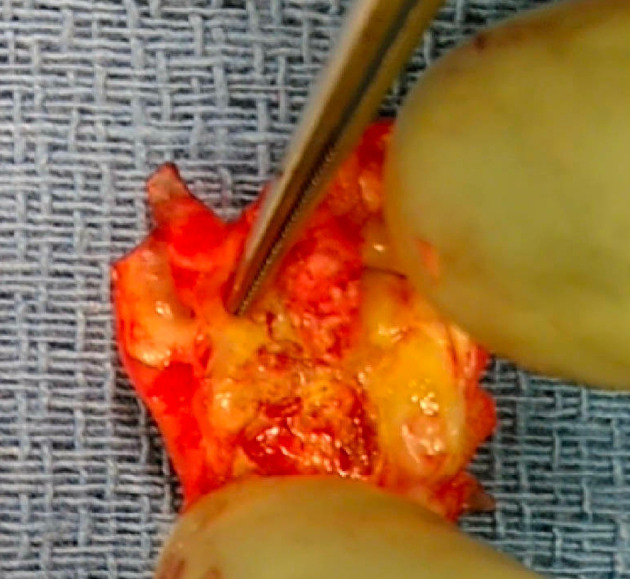

Internal carotid artery webs (ICAWs) have been described as noninflammatory, nonatherosclerotic shelf-like projections of intimal fibrous tissue which may be the culprit for embolic stroke of unknown origin. Carotid webs are an atypical form of intimal fibromuscular dysplasia (FMD) and internal carotid webs create areas of stagnation and recirculation distal to the web that favor thrombus formation and embolism. Symptomatic carotid webs are conventionally associated with young women presenting with few vascular risk factors and < 50% stenosis in the affected ICA. ICAWs are being described more and more in the vascular literature, but the management of this pathology remains unclear. We describe a rare case of a 90-year-old male who presented with a significantly sclerosed symptomatic right ICAW without evidence of comorbid atherosclerotic disease. The clinical management, intraoperative findings, and postoperative course are described herein. At the age of 90, this patient is the oldest case of symptomatic carotid web recorded in the literature. Successful management with a carotid endarterectomy is an appropriate strategy for treatment even in a nonagenarian. We would favor carotid endarterectomy over carotid artery stenting given the circumferential, fibrotic nature of these lesions.